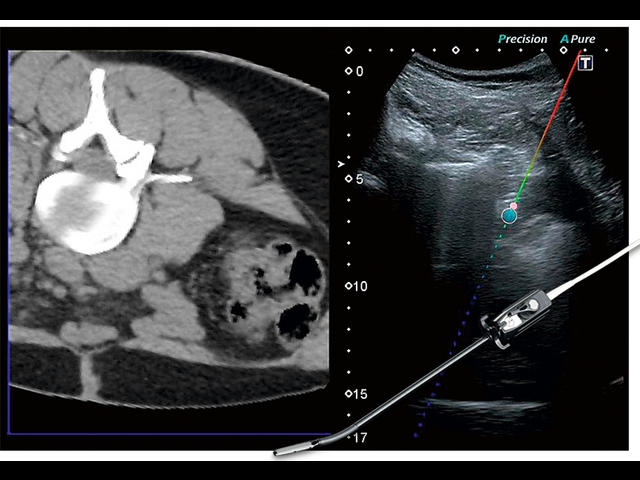

Обновленная версия легендарного УЗ-сканера. Стационарный аппарат экспертного класса Aplio 500 Toshiba NEW, визуализирует анатомические структуры в высоком разрешении. Модель позволяет выявить микрокальцификаты, новообразования, нарушения в работе сердца, сосудов и мышц. Присутствует функция виртуальной эндоскопии, 4D-сканирования, эластометрии тканей, УЗИ с контрастированием. За повышение качества изображения отвечают технологии ApliPure и Superb Microvascular Imaging. Первая задействует возможности пространственного и частотного кодирования, формирует цельный визуальный ряд с сохранением клинических маркеров. Вторая улучшает отображение микрососудистого русла, используя доплеровский эффект. Модель оснащена 21-дюймовым монитором, имеет 4 активных порта. Возможно подключение педиатрических, интраоперационных, лапароскопических и чреспищеводных датчиков.

• Fly Thru. Виртуальная эндосонография обеспечивает построение трехмерной модели полостей, протоков и сосудов в рельном времени, облегчает организацию инвазивных процедур и динамических исследований. Посредством Fly Thru можно установить шунты и стенты, проводить точные оперативные вмешательства.

IFusion: